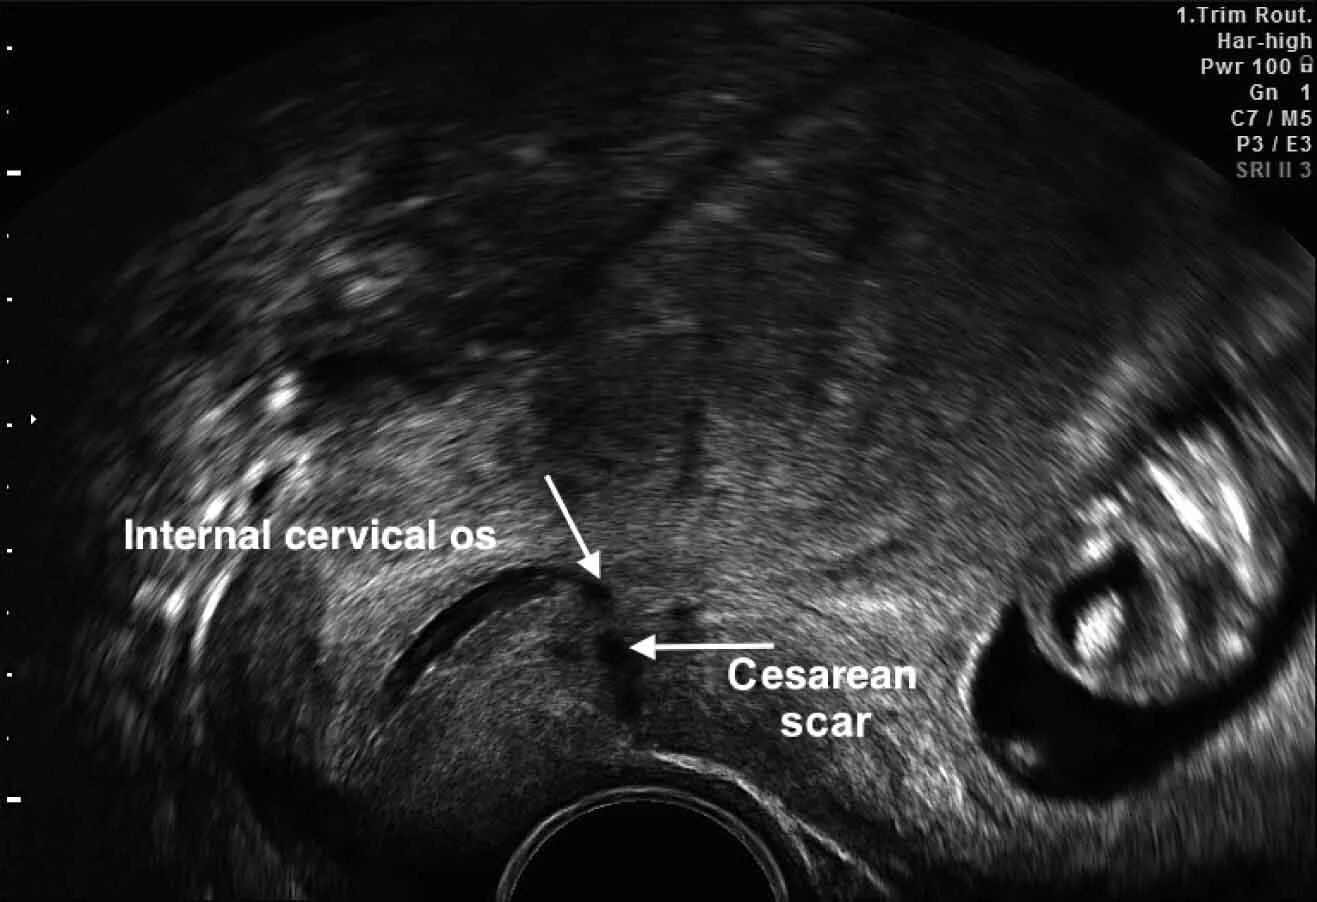

Оценка рубца на матке после кесарева сечения. рубец на матке норма. рубец на матке после кесарева сечения толщина норма. нормальная толщина рубца на матке после кесарева.Состоятельность рубца на матке после кесарево узи. узи рубца на матке при беременности. рубец на матке после кесарево узи. несостоятельный рубец на матке узи.Критерии несостоятельности рубца на матке. толщина рубца на матке после кесарева. локализация рубца на матке. рубец на матке норма.Узи несостоятельность рубца на матке. по узи несостоятельность рубца после кесарева сечения. состоятельность послеоперационного рубца на матке узи. несостоятельность рубца на матке после кесарева узи.Узи несостоятельность рубца на матке. узи матки после кесарева сечения. рубец после миомэктомии узи.Узи критерии несостоятельного рубца. критерии несостоятельности рубца на матке. несостоятельность рубца на матке. признаки несостоятельности рубца на матке.Аденомиоз рубца на матке после кесарева. эндометриоз кожного рубца узи. эндометриоз по рубца узи.Несостоятельность рубца на матке после кесарева сечения. критерии несостоятельности рубца на матке. состоятельность рубца на матке после кесарева. несостоятельность шва на матке.Ведение беременной с рубцом на матке. ведение родов у женщин с рубцом на матке. оценка состояния рубца на матке. критерии состоятельности рубца на матке.Показания к операции кесарево сечение при тазовом предлежании плода. показания к кесареву сечению при тазовом предлежании. показания к операции кесарево сечение при тазовом предлежании. толщина рубца на матке после кесарева норма.Узи рубца на матке при беременности. рубец на матке после кесарево узи. узи матки после кесарева сечения.Узи несостоятельность рубца на матке. несостоятельный рубец на матке узи. несостоятельность рубца на матке после кесарева сечения узи. толщина рубца на матке на узи.Рубец от кесарева на узи.Состоятельность рубца на матке. неполноценность рубца на матке.Полноценный рубец на матке. расхождение рубца на матке при беременности. послеоперационный рубец на матке норма. несостоятельность рубца на матке мрт.Толщина рубца на матке 5.2. критерии несостоятельности рубца на матке. рубец после кесарева сечения норма по узи. несостоятельность послеоперационного рубца на матке по узи.Рубец на матке после кесарева сечения толщина норма. измерение рубца на матке по узи. узи несостоятельность рубца на матке. рубец на матке после кесарева сечения по узи.Рубец на матке на узи описание. узи несостоятельность рубца на матке. узи рубца на матке при беременности. несостоятельность шва после кесарева сечения на узи.Врастание плаценты на узи. врастание плаценты в рубец на матке узи. эхограмма врастания плаценты. врастание плаценты в рубец на матке.Критерии несостоятельности рубца на матке. рубец матки после операции. локализация рубца на матке.Рубец на матке 1 1Узи послеоперационного рубца. несостоятельность послеоперационного рубца. несостоятельный рубец на матке узи.Нормальная толщина рубца на матке после кесарева сечения. толщина рубца на матке при беременности норма. норма толщина рубца на матке. норма толщины рубца на матке по неделям беременности после кесарева.Рубец на матке 1 1Признаки несостоятельности рубца. несостоятельность рубца на матке. симптомы несостоятельности рубца на матке. критерии несостоятельности рубца на матке.Несостоятельность шва после кесарева сечения на узи. несостоятельный рубец на матке узи. узи несостоятельность рубца на матке.Узи несостоятельность рубца на матке. несостоятельность рубца на матке после кесарева сечения узи. рубец на матке на узи описание. несостоятельность шва после кесарева сечения на узи.Ультразвуковым признаком врастания плаценты является. врастание плаценты в рубец форум.Узи состоятельный рубец на матке. узи несостоятельность рубца на матке. узи рубца на матке при беременности.Рубец на матке после кесарева сечения узи.Несостоятельность рубца на матке после кесарева. несостоятельность рубца на матке после кесарева по узи. локализация рубца на матке после кесарева сечения. нормы рубца на матке после кесарева сечения.Несостоятельность рубца узи. узи несостоятельность рубца на матке. по узи несостоятельность рубца после кесарева сечения. несостоятельность рубца на матке после кесарева по узи.Презентация рубец на матке. рубец на матке мкб 10 код. мкб несостоятельность рубца на матке после кесарева. диагноз рубец на матке.Узи несостоятельность рубца на матке. узи рубца на матке после кесарева.Рубец на матке после кесарево узи. толщина рубца на матке на узи. беременность в рубце на матке узи.Несостоятельность рубца на матке после кесарева по узи. несостоятельность рубца на матке после кесарева узи. несостоятельность послеоперационного рубца.Несостоятельность рубца на матке после кесарева узи. несостоятельность шва после кесарева сечения на узи.Узи после кесарева сечения. шов на матке после кесарева заключение узи.Нормы рубца на матке после кесарева сечения. нормальная толщина рубца на матке после кесарева сечения. рубец на матке при беременности норма. норма толщины рубца на матке по неделям беременности.Рубец на матке 1 1